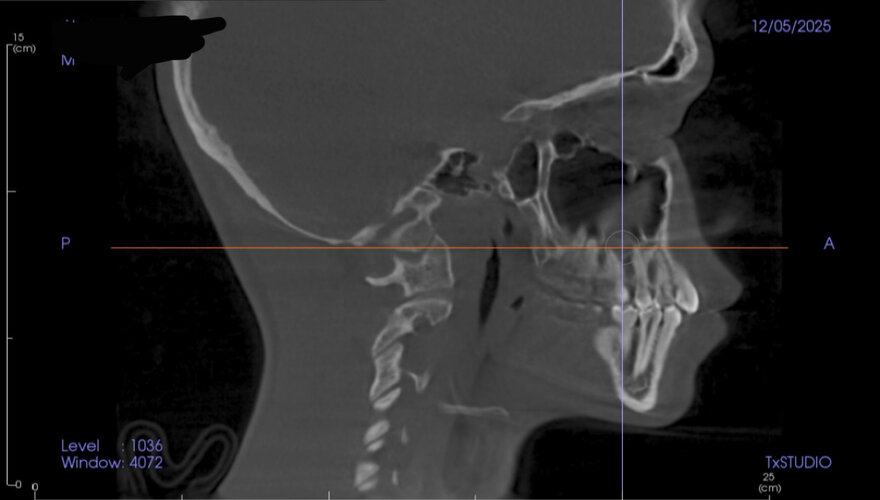

Went to the orthodontist the other day and got these scans. I’m trying to figure out what I should change or improve to look better. Based on this, what do you think needs work and what can I do to improve it?